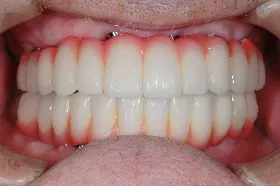

咀嚼障害のため来院されたケース(all-on-4)

60代 男性

咀嚼障害、歯茎の痛みを訴えられ、来院されました。

■治療前

■治療後

| 主訴 | かみにくい・全体的に歯茎が腫れて痛みがある 痛みがある |

| 治療方法 | 上下顎に複数本のインプラントを使用し、一体型の補綴物をセット |

| 治療期間 | 約1年 |

| 通院回数等 | 約20回 |

| 費用 | 約600万円 |

| リスク・副作用 | 補綴物が過度な力で破損するリスクがある |